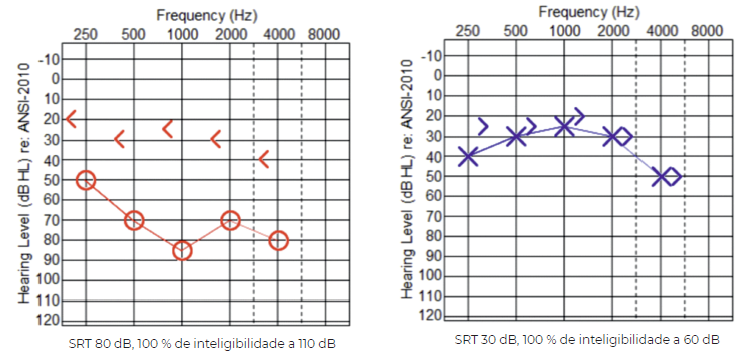

A audiometria tonal (figura 2 ) e vocal mostrava à direita uma surdez mista severa, com GAP áereo-ósseo (AO) de 40 a 60 dB nas frequências conversacionais e com um Speech Recognition Threshold (SRT) de 80 dB e 100 % de inteligibilidade a 110 dB. À esquerda mostrava uma surdez neurossensorial ligeira, com um SRT de 30 dB e 100 % de inteligibilidade a 60 dB.